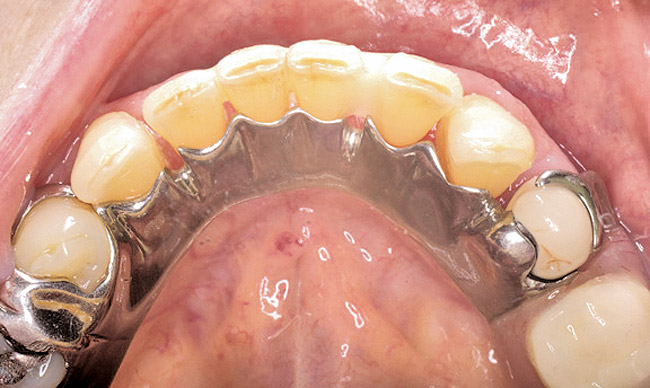

Figure 13  Occlusal view of composite splint.

Figure 13

Under the sextant approach, one quadrant is treated and the patient is left to heal for 2 months before proceeding to any additional quadrants. While the patient heals, a 10-day course of antibiotics and 2 months of twice-daily chlorhexidine rinsing may be prescribed. Figure 4 shows a patient who was taking oral bisphosphonates for 3 years and was treated with the sextant approach. As seen in the radiograph, the patient has one molar in the lower right quadrant. This tooth was extracted and the patient was given 2 months to heal (Figure 5 and Figure 6). The patient was placed on antibiotics and chlorhexidine rinse. After 2 months, no signs of BRONJ were observed, and the anterior teeth were scheduled for extraction. They were extracted as atraumatically as possible, and the site was sutured (Figure 7 and Figure 8).The patient then was given another 2 months to heal, following the previous protocol. After 2 months of healing, no BRONJ was observed (Figure 9).

Then, patient was able to move forward with the prosthesis. Figure 10 shows a periodontal patient who was taking oral bisphosphonates for osteoporosis. The patient had full-mouth scaling and root planing, then was given 2 months to heal and instructed to rinse with chlorhexidine twice daily. After no signs of BRONJ were observed, the patient had full-mouth osseous surgery on her few remaining teeth in the mandible. The surgery was performed all at once and not according to the sextant approach because the patient was on a heart and lung transplant list and was moved up the list while healing from the scaling and root planing. The patient also had extensive bone loss in her anterior mandible (Figure 11).To avoid performing extractions, a simple composite splint was placed between the partial dentures (Figure 12 and Figure 13). The splint reduced the mobility of the teeth and made them less likely to be knocked out during any surgical intubation procedure.